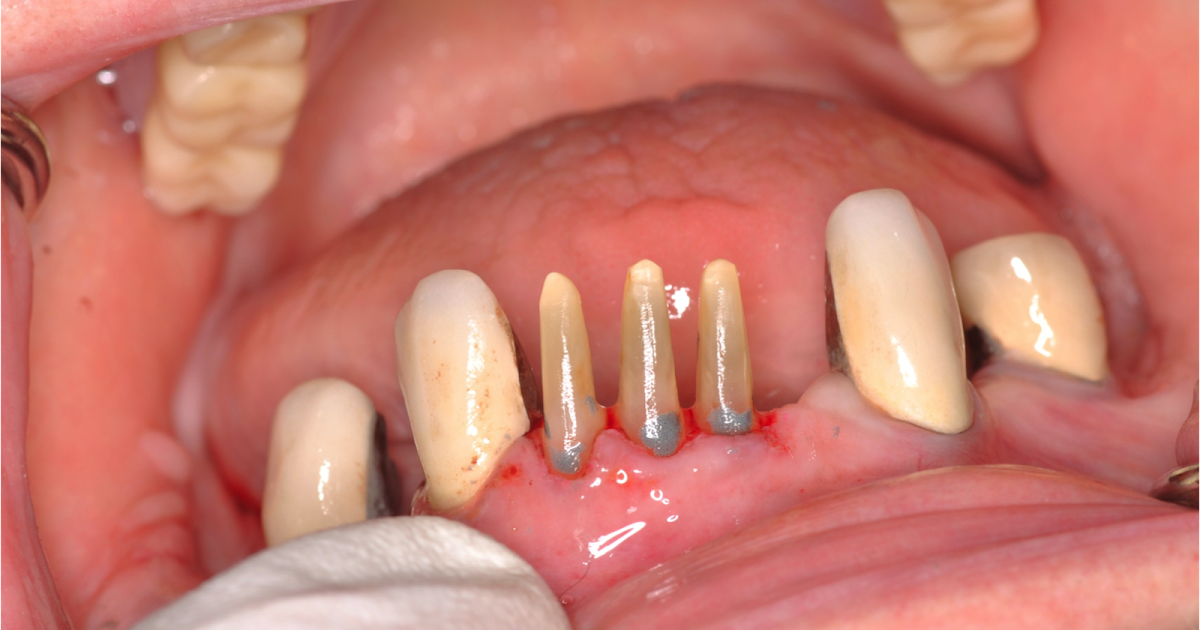

From www.youtube.com

Chamfer prep on a live patient YouTube Chamfer Vs Shoulder Crown Prep this article aims to identify some principles that can assist dentists to design, assess and modify complete coverage. Marginal width more than 0.3mm: marginal width up to 0.3mm: the biggest difference is in the choice of burs and how to utilize the correct diameter diamond to get the desired. It is the type of tooth. the. Chamfer Vs Shoulder Crown Prep.